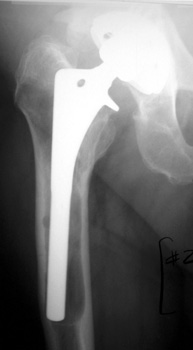

COMPONENT MIGRATION

ACETABULAR CUP

ACETABULAR COMPONENT

Progressive protrusio and tilt

Migrating acetabular cup

Very abnormal positioned cup. No comparison radiographs were available. Current radiographs demonstrates markedly tilted cup which has migrated laterally from pelvis.